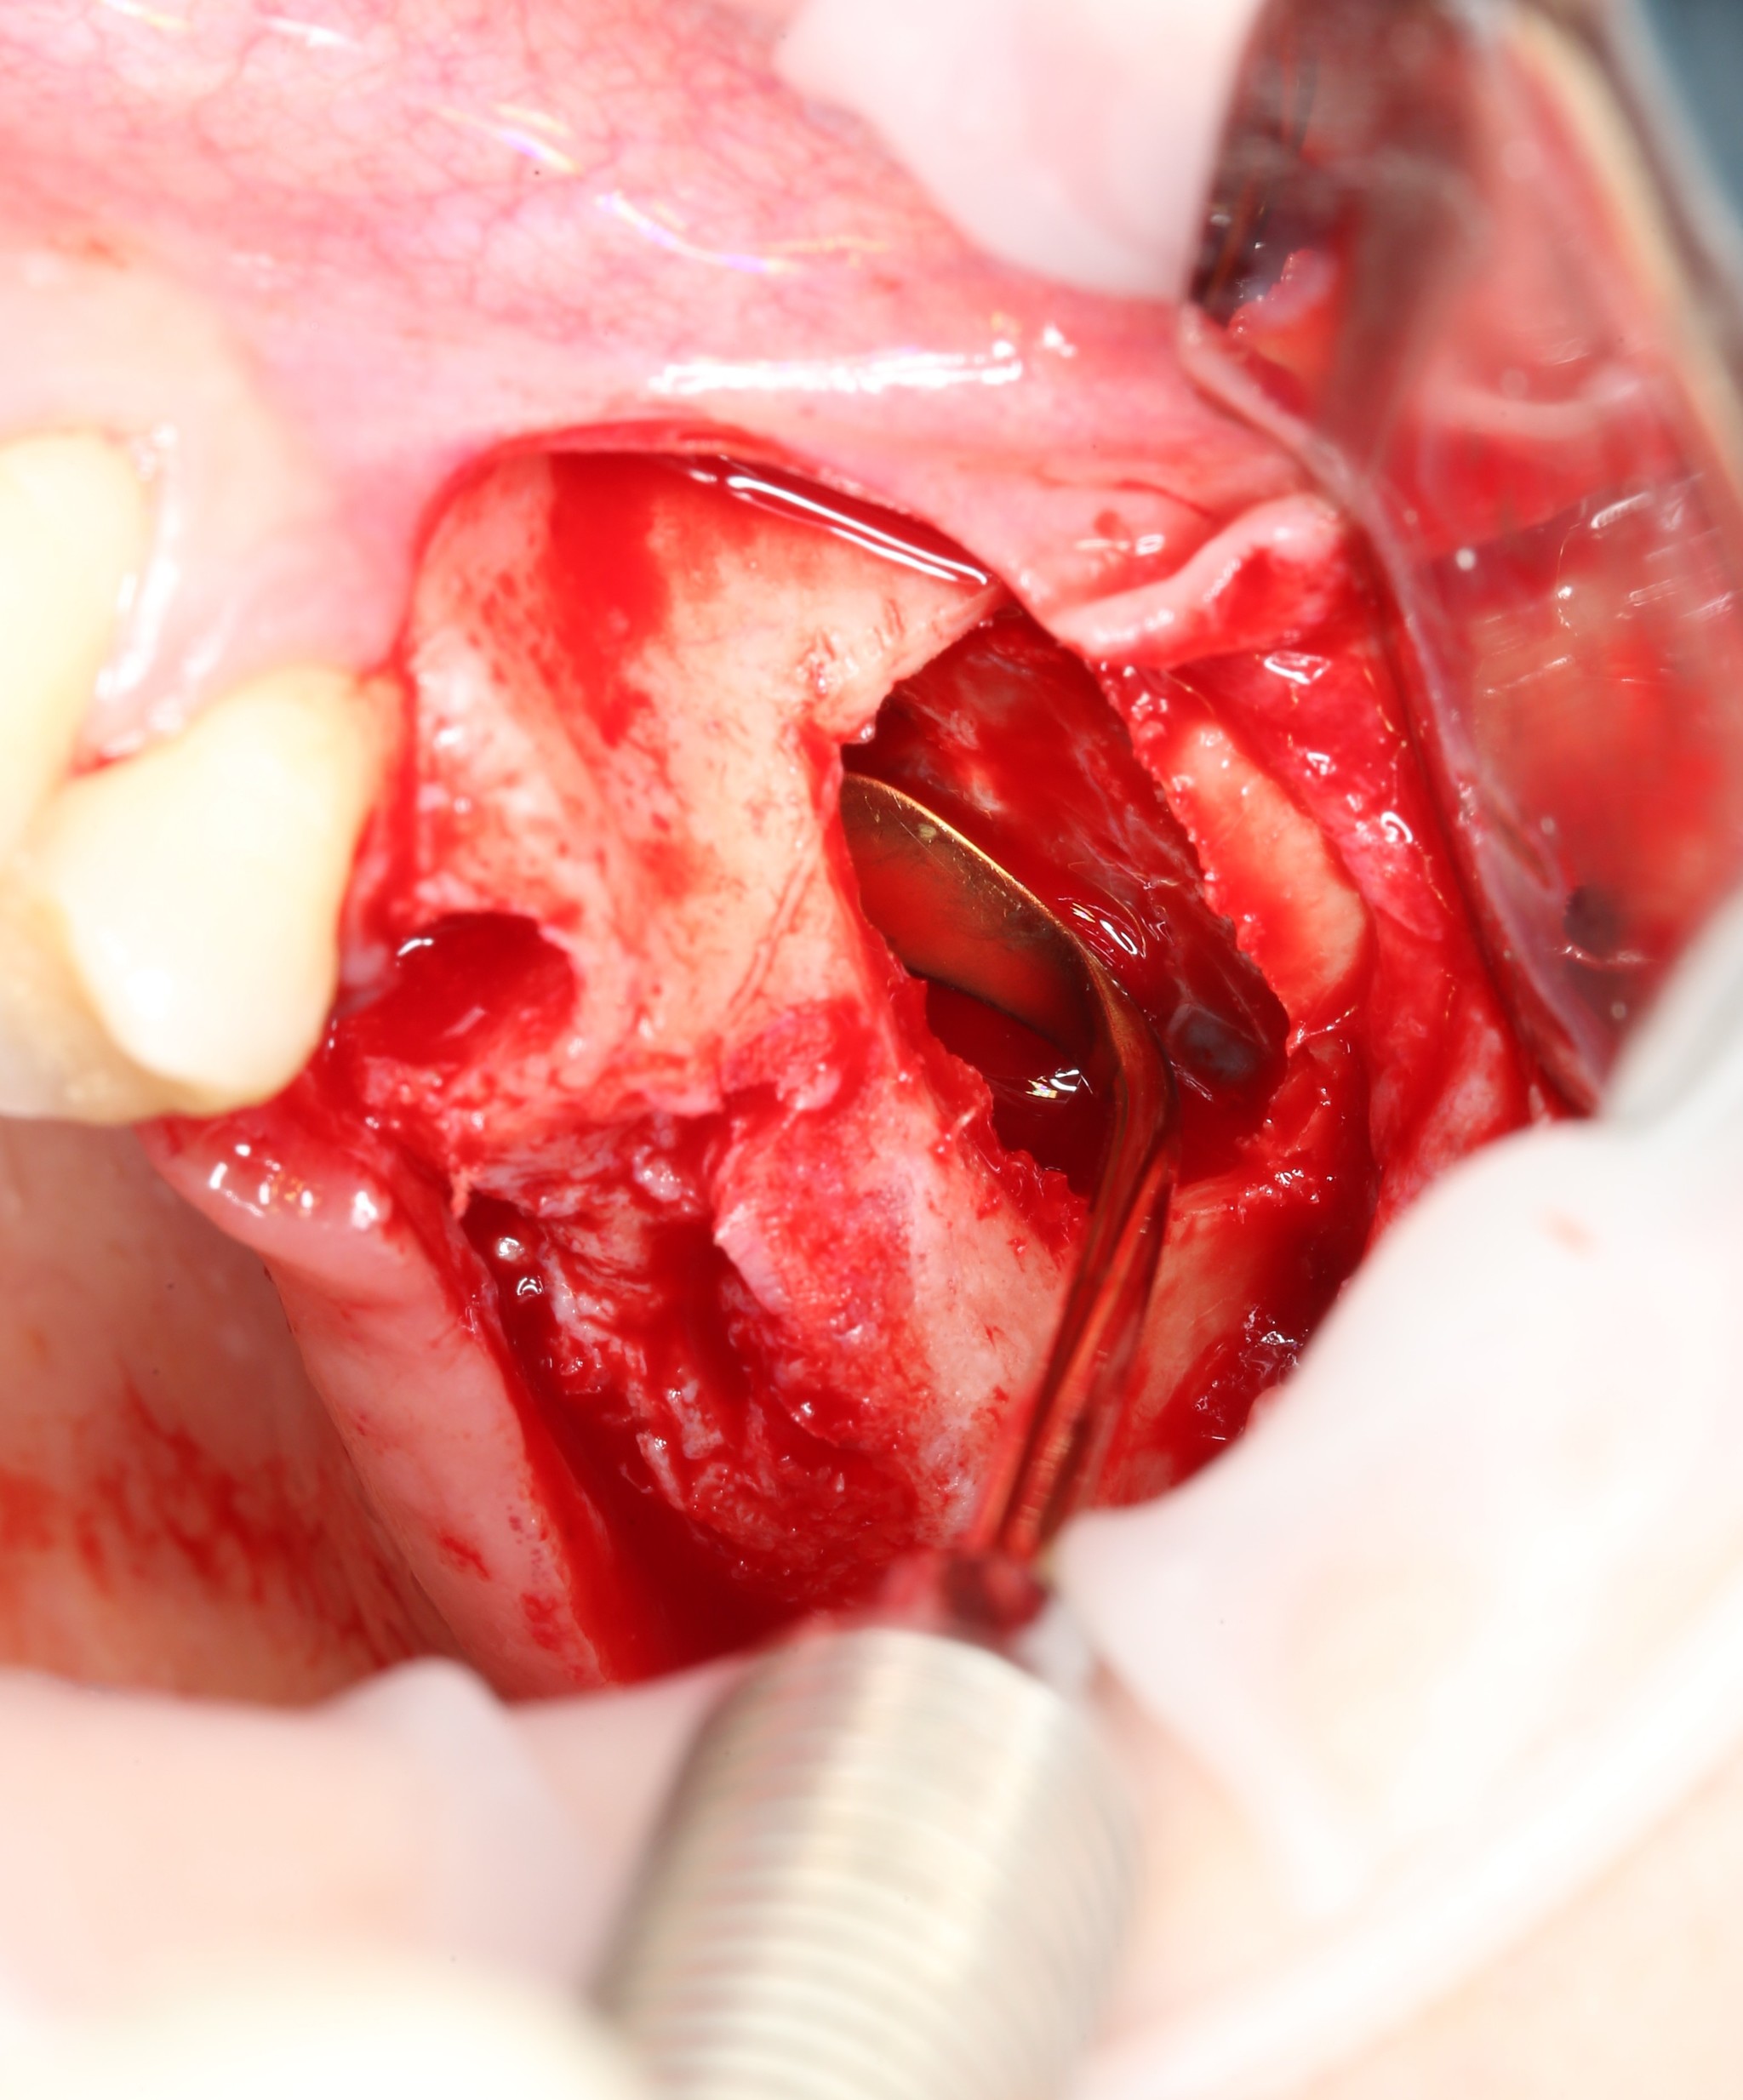

На очереди сам синус-лифтинг.

Ошибочно полагать, что синус-лифтинг — это операция «В» верхнечелюстной (Гайморовой) пазухе. На самом же деле манипуляция проводится «ПОД» ней.

Как мы уже выяснили, пазуха — это полость на верхней челюсти, пустота, если хотите, которая выстлана изнутри тонкой слизистой оболочкой. Местно проводится отслоение слизистой оболочки от костной ткани, а в сформировавшееся пространство между дном пазухи и слизистой оболочкой, как в конверт, помещается костный материал.

Данная манипуляция проводится при помощи специальных кюрет, рабочая часть которых загнута под разными углами. Это позволяет произвести отслоение слизистой оболочки в любых труднодоступных местах:

Но нужно быть аккуратным, потому как любое неосторожное движение может привести к разрыву отношений слизистой оболочки.

Если перфорация небольшая, то его легко устранить. Для этого используется рассасывающаяся мембрана, которой эта перфорация закрывается. После чего операцию можно продолжать.

В сформировавшийся карман укладывается гемостатическая губка, смоченная в физ. растворе:

Это необходимо для того, чтобы не повредить слизистую в момент формирования ложа под имплантат сверлом.